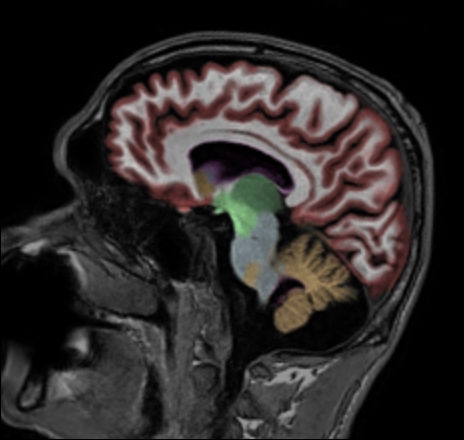

Sagittal 3D T1w TFE with NeuroQuant segmentation